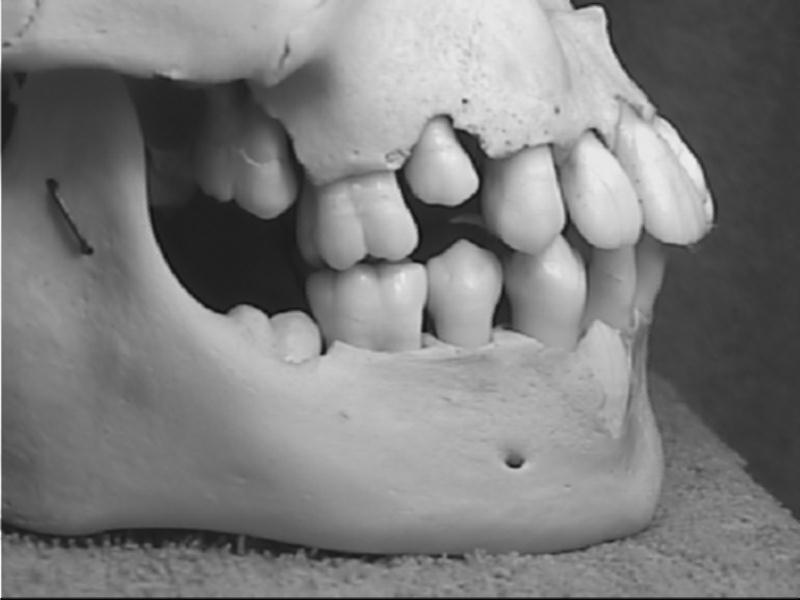

Sơ đồ mầm răng sữa trẻ 6 tuổi trên xương hàm, trẻ đã mọc đủ răng cửa sữa số 1, 2 , 3, 4 và 5 ký hiệu bằng màu xanh trong miệng, Dưới chân các răng sữa trong xương hàm là mầm răng vĩnh viễn tương ứng có màu vàng. Hình ảnh tiêu chân răng cửa sữa số 1 và 2 nhiều hơnHàm răng sữa khi bắt đầu xuất hiện răng vĩnh viễn đầu tiên đến khi thay chiếc răng sữa cuối cùng gọi là Hàm hỗn hợp | Xương sọ vùng hàm trên và dưới trẻ 6 năm tuổi. Theo thứ tự từ Trái qua Phải hàm trên là số 7, số 6, số 5 vĩnh viễn mới nhú, số 4, 3, 2, 1 sữa. hàm dưới là số 7, số 6, số 5, 4, 3, 2, 1 sữa |

Xuơng sọ vùng hàm trên và dưới trẻ 11-12 tuổi, Từ trái qua phải là răng số 7, 6, 5, 4, 3, 2, 1 |